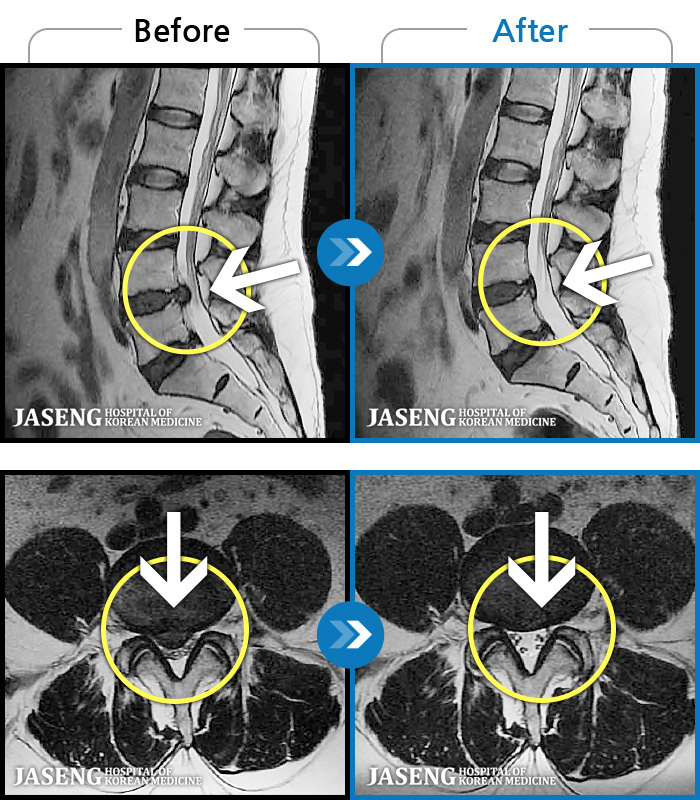

123 MRI ũ ʸ Ȯϼ.

ó ̾ ߰, ణ ٷϵ ݵǾ ϻȰ ¿ϴ. |

[õ] 24.04.06~24.11.16